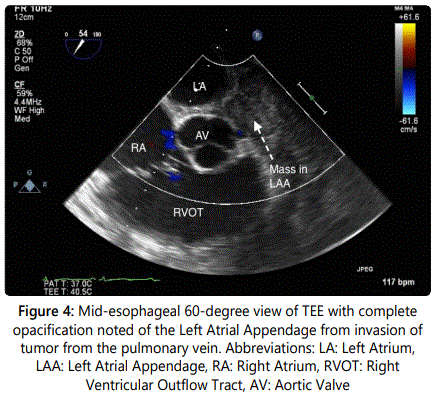

A 54-year-old gentleman with recently diagnosed Stage IIIB squamous cell carcinoma of the lung with metastases to the lymph nodes had a transthoracic echocardiograph (TTE) performed for evaluation of progressive dyspnea on exertion. A large pericardial effusion causing tamponade physiology was noted on TTE and the Computerized Tomography (CT) image of the thorax (Figures 1 and 2). Following a pericardi ocentesis, a repeat TTE was performed which showed the presence of a left atrial mass (Figure 3). The mass was initially reported as a 1.3x0.5 cm pedunculated mobile left atrial mass arising from the left atrial appendage prolapsing in the mitral orifice in diastole before further assessment with a transesophageal echocardiogram (TEE) was performed. The TEE demonstrateddirect invasion of the mass from the left upper pulmonary vein into the left atrial appendage with minimal residual flow of that pulmonary vein and complete opacification of the left atrial appendage as well as invasion of the superior vena cava (Figure 4). The mobile mass in the left atrium was a strand of tumor that extended from the edge of the left atrial appendage (Figures 5 and 6).

Metastases to heart are significantly more common than primary cardiac tumors with an approximate 20-40x the prevalence of that of primary tumors [1,2]. While historically a post-mortem finding, cardiac metastases are becoming increasingly diagnosed in living individuals with advances in imaging modalities including echocardiography (TTE and TEE), CT, MRI, and Positron Emission Tomography [3,4]. Here, we describe a rare example of direct invasion from squamous cell carcinoma of the lung of a mobile mass in the left atrium on TTE that was better visualized with TEE.